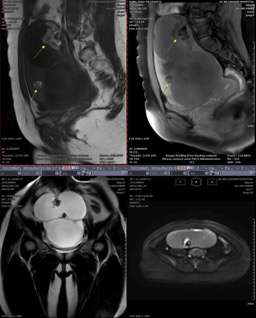

圖2 成熟型畸胎瘤 病變巨大,囊壁較均勻,可見少許分隔,邊界清楚,黃色箭所指為脂肪成份,可明確診斷。